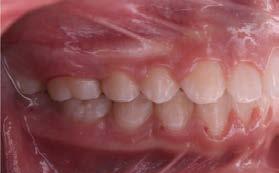

Objetivos: Conseguir clase I canina, controlar el crecimiento vertical, disminuir la convexidad esqueletal, reducir la sobremordida horizontal y mejorar el perfil facial. Caso clínico: Paciente femenina de 9 años, clase II esqueletal, biotipo dolicofacial, perfil convexo, clase II molar, clase II canina y proinclinación de incisivos superiores e inferiores. Resultados: Se logró clase I canina, se controló el crecimiento vertical, se redujo la convexidad esqueletal, se mejoró la sobremordida horizontal y el perfil facial. Conclusiones: El uso combinado de aparatos ortopédicos y aparatología fija en pacientes en crecimiento, junto con un diagnóstico y plan de tratamiento acertado, permite obtener resultados exitosos y estables en la corrección de estas maloclusiones.

La relación maxilomandibular desempeña un papel importante en la posición de los molares y puede clasificarse como clase I, II o III, de acuerdo con la clasificación de Angle. Esqueletalmente, esta relación solo puede determinarse mediante estudios radiológicos; los modelos de estudio solo ofrecen una aproximación clínica.1